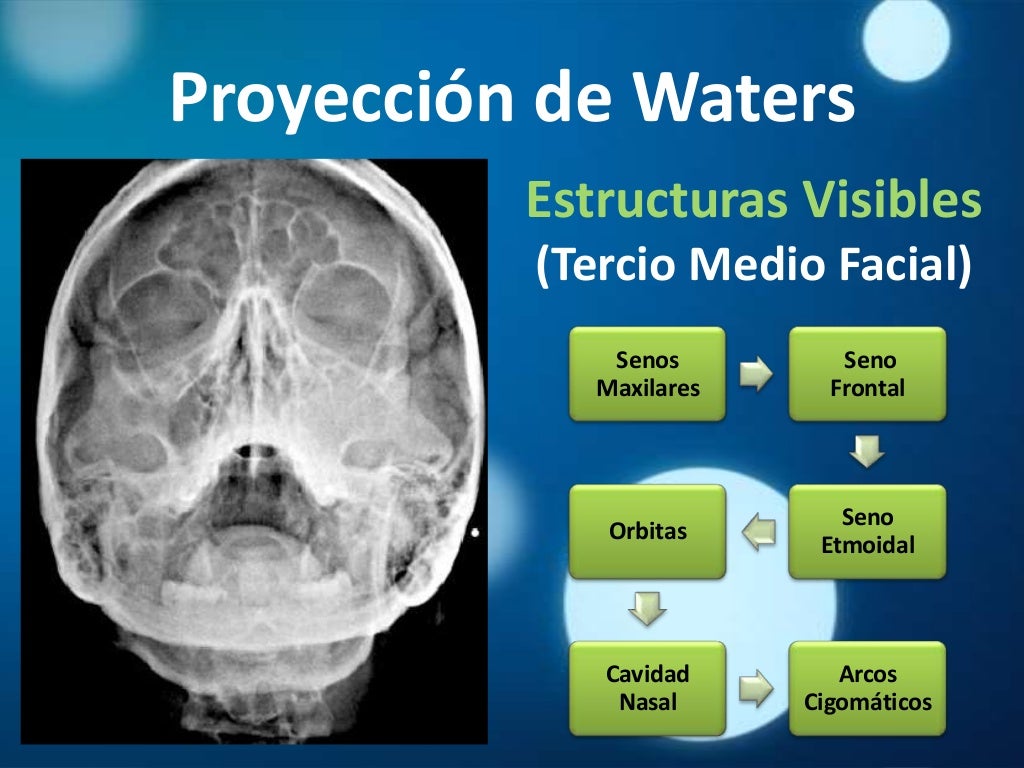

Radiología Tecnica de Waters - Descargar como PDF o ver en línea de forma gratuita. Proyeccion ap, lateral y oblicua del pie HillaryPerez7. Forma parte de serie radiográfica para evaluación de senos paranasales, junto a RX Caldwell y lateral de cráneo 4. La proyección de water es muy útil para estudiar el piso de la órbita,.

El estudio de "Rx Senos Paranasales 3 Proyecciones (Waters, Caldwell y Lateral)" implica la captura de imágenes radiográficas de los senos paranasales desde tres direcciones diferentes utilizando las técnicas de Waters, Caldwell y lateral. 1. **Técnica Waters**: En esta proyección, el paciente se coloca de pie o sentado con la cabeza.

Estudio de la identificación de las distintas estructuras que podemos describir en una Rx de cráneo (water)

El estudio de "Rx Senos Paranasales 1 Proyección (Waters, Caldwell o Lateral)" implica la toma de una radiografía de los senos paranasales desde una sola dirección utilizando una de las siguientes técnicas: Waters, Caldwell o lateral. 1. **Técnica Waters**: En esta proyección, el paciente se coloca de pie o sentado con la cabeza.

La opción ideal en la sospecha de cualquier traumatismo craneofacial es la TC. En caso de no disponer de tomografía, las proyecciones de radiología convencional más apropiadas en estas situaciones son: el Waters (occipitomental), la proyección de Caldwell (occipitofrontal), la lateral y la proyección de Hirtz o de arcos cigomáticos.

grupos de senos. Proyección PA axial (Método Cadwell): Senos frontales y etmoidales anteriores. Proyección de Waters (Parietoacantial): con boca cerrada: Senos maxilares Proyección de Waters (Parietoacantial) con boca abierta: Senos maxilares y esfenoidales. Proyección Submentovertical: Senos etmoidal y esfenoidal. Centraje: Línea.